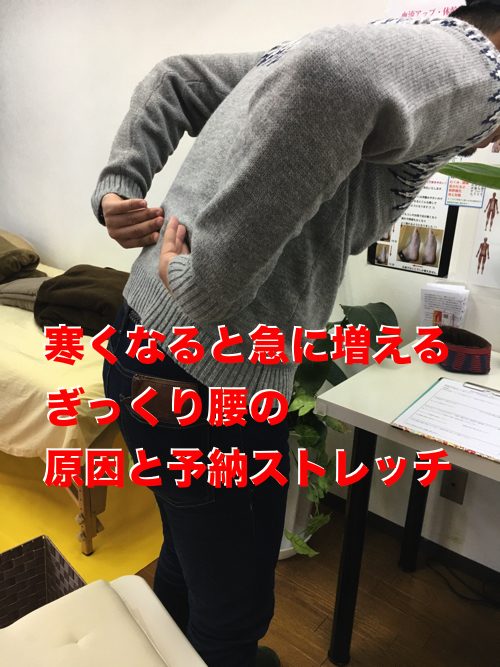

日頃から疲れの溜まった筋肉や腱は特に

寒くなると筋肉や腱の柔軟性が損なわれて固くなり

ふと力を入れた際や

何気なくしゃがんだ際に

激痛を生む「ぎっくり腰」になってしまう事が多々あります。

今回のお客様もふとした動きの際に腰に激痛・・・・

そんな状態でネット予約でご来院下さいました。

痛みの出る場所はここ。

前かがみになると特に激痛。

起き上がった状態では痛みが半減します。